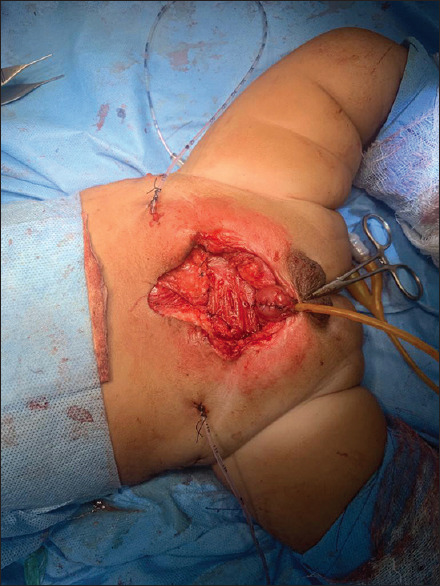

Background: Wound dehiscence is one of the main complications in complete primary repair of exstrophy (CPRE). In our pediatric urology unit, we have switched to the use of inferior epigastric artery based rectus abdominis flap cover for abdominal wall closure in addition to measures like osteotomy and postoperative hip spica.

Methods: This study was conducted from June 2014 to June 2021 comparing two groups of the patients; group I consisted of thirty patients of CPRE with rectus flap repair of abdominal wall (CPRE-RF) and group II consisted of thirty patients with CPRE without rectus flap. Clinical and surgical details, including the outcome with regards to wound dehiscence and continence, were recorded.

Results: The mean age of the patients in CPRE-RF was 5 months and that with only CPRE was 4.6 months. Mean pubic diastasis in Group l was 4.8± 1.07 cm and that of Group II was 4.6±1.3 cm. None of the patients in CPRE-RF had wound dehiscence or bladder prolapse while as 6 patients in CPRE alone had wound dehiscence and 1 had bladder prolapse. This difference was statistically significant. Primary bladder continence was achieved in 4 patients in CPRE-RF and 3 patients in CPRE group. Hypospadias had almost similar occurrence in the two groups. One patient in each group had bladder neck fistula.